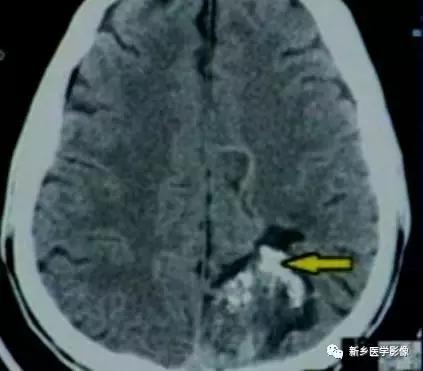

十七、动静脉畸形(AVM)

A VM发生钙化较为常见,主要与血栓形成及反复出血有关,钙化可呈小点状或不规则小片状,也可呈团块状或许多血管条形钙化